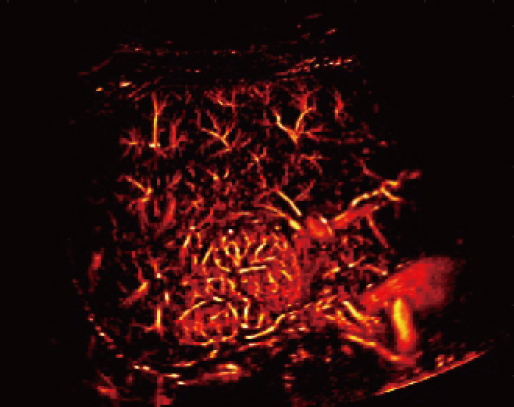

Resona A20 supports clinicians in cutting-edge clinical research. Super

Resolution CEUS (SR CEUS) reveals blood perfusion details at the micron

level, aiding clinicians in the exploration of early microcirculatory

changes in lesions. Additionally, STVi shear wave viscoelastography, a

Powered by the AIT platform, the Resona A20 delivers an all-in-one

integrated solution for super-resolution imaging, a capability

previously difficult to achieve. SR CEUS reveals the intricate

microcirculation details of lesions at the micron level, aiding in

microcirculatory perfusion studies in oncology.

Microvascular detection capabilities

Focal Nodular Hyperplasia | Density Map

Focal Nodular Hyperplasia | Direction Map

Focal Nodular Hyperplasia | Velocity Map